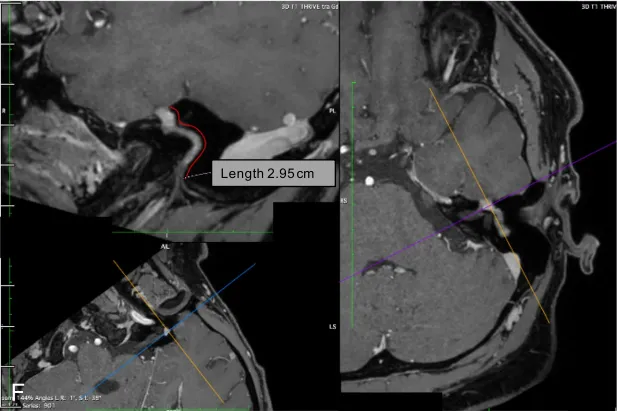

注射钆对比剂后肿瘤呈现显著强化,T2加权像呈高信号,T1加权像呈等或低信号(图1)。三维稳态构成干扰序列或三维快速成像序列可提供重要诊断信息。

对于位于桥小脑角及内耳道的肿瘤,其与前庭神经鞘瘤的鉴别诊断存在困难甚至难以区分。若肿瘤延伸至面神经迷路段,则支持面神经鞘瘤的诊断。位于脑池段及内耳道的大型面神经鞘瘤可呈现与前庭神经鞘瘤相似的"哑铃形"形态,此征象源于肿瘤穿过内耳道,扩大面神经管并进入膝状神经节窝。

增强T1序列可清晰显示肿瘤强化,结合CT显示的骨质改变,可使面神经鞘瘤成为符合上述影像特征的首要鉴别诊断。极少数情况下,面神经鞘瘤可表现为中颅窝占位病变,可能源于膝状神经节肿瘤沿岩浅大神经蔓延,或原发于岩大神经本身的肿瘤。此类情况需与三叉神经鞘瘤相鉴别。这些肿瘤通常体积较大,仔细分析颞骨影像若发现面神经通路其他节段受累,即可明确面神经鞘瘤的诊断。